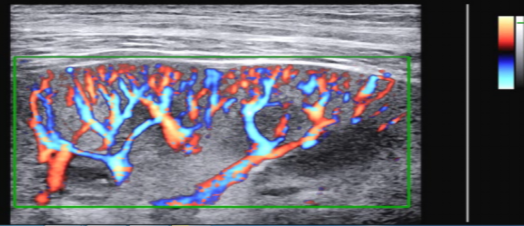

S-FlowTM  精细血流成像技术

通过创新的超高灵敏度彩色多普勒检测出细微血管和低速血流信号,这种先进的多普勒技术能够使血流动力栩栩如生,更加逼真;脐动脉、甲状腺腺瘤、肾脏血管使用效果明显;并且不受病人生理机能影响提供最准确的诊断。